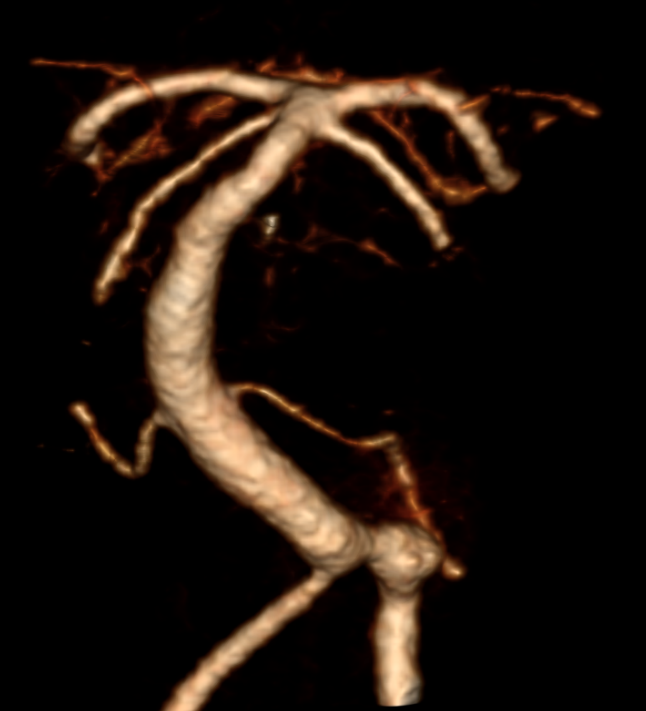

Der Goldstandard zur optimalen Darstellung der Arteria vertebralis ist die digitale Subtraktionsangiographie, kann jedoch je nach klinischer Fragestellung auch in der CT-Angiographie oder MRT Bildgebung dargestellt wird.

Im Bereich der Arteria vertebralis können typischerweise Dissektionsaneurysmen auftreten und eine Subarachnoidalblutung verursachen[^3]. Die Behandlung dieser Dissektionsaneurysmen kann je nach Fall beispielsweise endovaskuläre mithilfe von Implantation eines Flow-Diverters behandelt werden[^4] [^5].